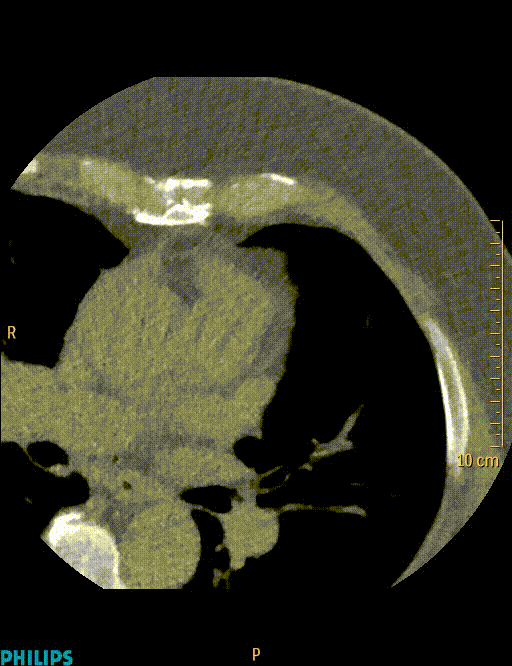

Coronary Calcium Scan

A CT Coronary Calcium test uses x-rays to obtain images of the heart to identify “hardening” of the coronary arteries. Calcium appears in the heart’s blood vessels as a marker of plaque that has been present for many years.

This is a relatively fast test and does not require any injections. You will be asked to lie flat on the CT table and some ECG leads are attached using sticky patches on your skin. This allows the scanner to be synchronised with the hear rhythm The table then goes into the “donut” of the CT machine. The CT scanner does deliver a small dose of radiation that approximately the same as a mammogram. The images are presented as slices taken through your body which allows the doctors to assess the calcium in the arteries. This can counted and quantified to provide a score, which is useful in estimating the chance of a heart attack in the future.